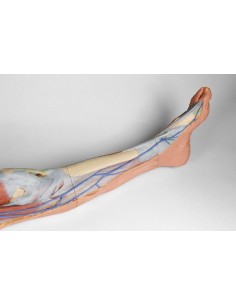

3D Anatomy 1.0 - Extremidades inferiores

Venas superficiales del miembro inferior Erler Zimmer 3D anatomy Series MP1815

3D Anatomy 1.0 - Extremidades inferiores

Disección superficial del miembro inferior Erler Zimmer 3D anatomy Series MP1816